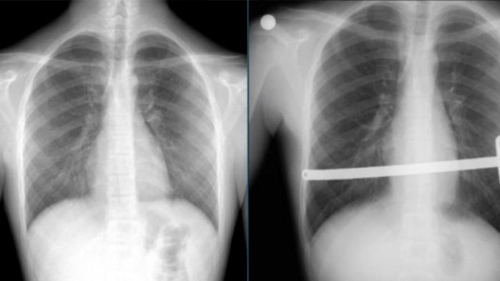

Nuss veya Abramson ameliyatı uygulayarak bar yerleştirdiğimiz Kunduracı Göğsü ve Güvercin Göğsü tanılı hastalarımızın ...